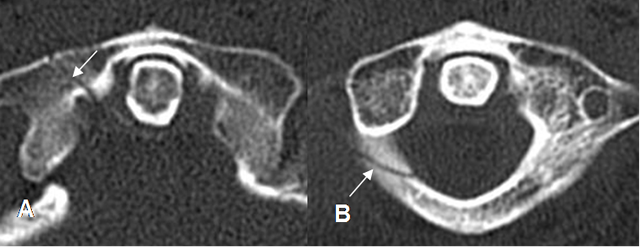

Fig 195. Fractura de C1.

A y B: TAC axial. Fracturas aisladas y no desplazadas de C1. En A del arco anterior y en B del arco posterior.